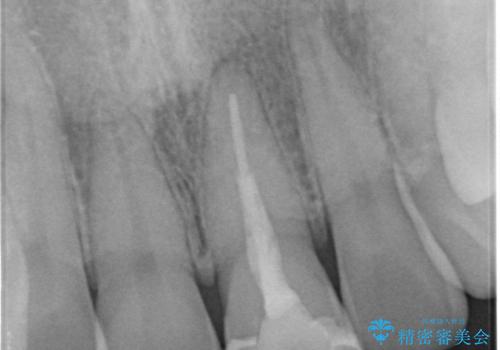

- 前歯の変色とガタつきが気になるとのことで来院された患者様です。

根管治療からやり直しを行った後、ジルコニアクラウンで修復することで、ガタつきと変色の両方を改善していきます。

- 左上1/再根管治療66,000円+ファイバーコア22,000円+仮歯11,000円+ジルコニアクラウン(スタンダード):121,000円 合計209,000円(税込)費用は治療当時の料金となります